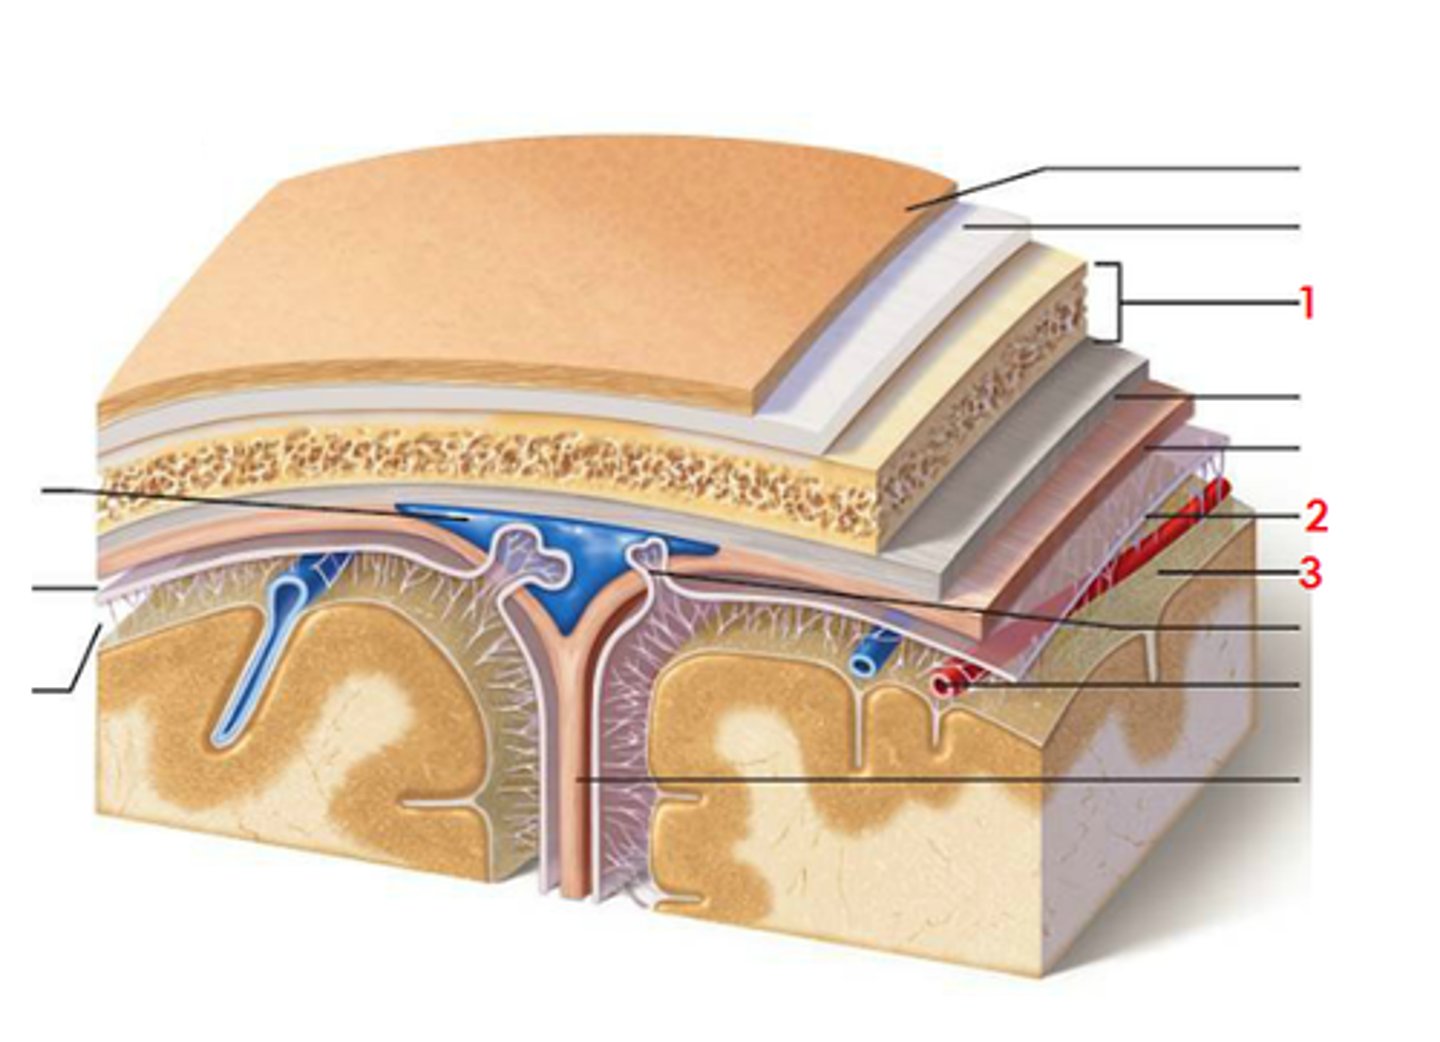

meninges

scalp, periosteium, then, 1st meningeal layer. Includes dura mater, arachnoid mater, and pia mater.

dura mater

2 layers. Periosteal layer (outer layer) and the meningeal layer - closest to next meningeal layer. This can create the dural venous sinus. right below 1 in this picture

arachnoid mater

meningeal layer on top. 2 in this picture

pia mater

sits directly on top of brain tissue. When CSF circulates, it circulates on top of brain tissue. If you try to tear pia mater away, you'll tear brain tissue. 3 in this picture